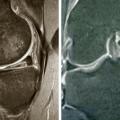

Lésion dégénérative du ménisque médial

LESIONS PERI-ARTICULAIRES

LESIONS LIGAMENTAIRES

Rupture du ligament croisé antérieur